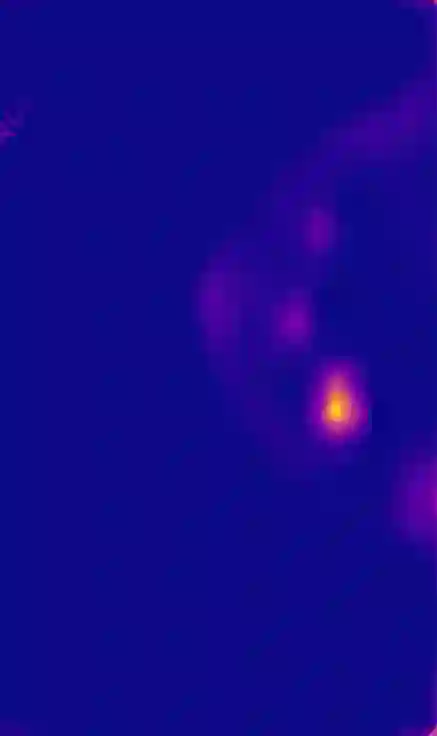

Breast cancer is the most widespread neoplasm among women and early detection of this disease is critical. Deep learning techniques have become of great interest to improve diagnostic performance. Nonetheless, discriminating between malignant and benign masses from whole mammograms remains challenging due to them being almost identical to an untrained eye and the region of interest (ROI) occupying a minuscule portion of the entire image. In this paper, we propose a framework, parameterized hypercomplex attention maps (PHAM), to overcome these problems. Specifically, we deploy an augmentation step based on computing attention maps. Then, the attention maps are used to condition the classification step by constructing a multi-dimensional input comprised of the original breast cancer image and the corresponding attention map. In this step, a parameterized hypercomplex neural network (PHNN) is employed to perform breast cancer classification. The framework offers two main advantages. First, attention maps provide critical information regarding the ROI and allow the neural model to concentrate on it. Second, the hypercomplex architecture has the ability to model local relations between input dimensions thanks to hypercomplex algebra rules, thus properly exploiting the information provided by the attention map. We demonstrate the efficacy of the proposed framework on both mammography images as well as histopathological ones, surpassing attention-based state-of-the-art networks and the real-valued counterpart of our method. The code of our work is available at https://github.com/elelo22/AttentionBCS.